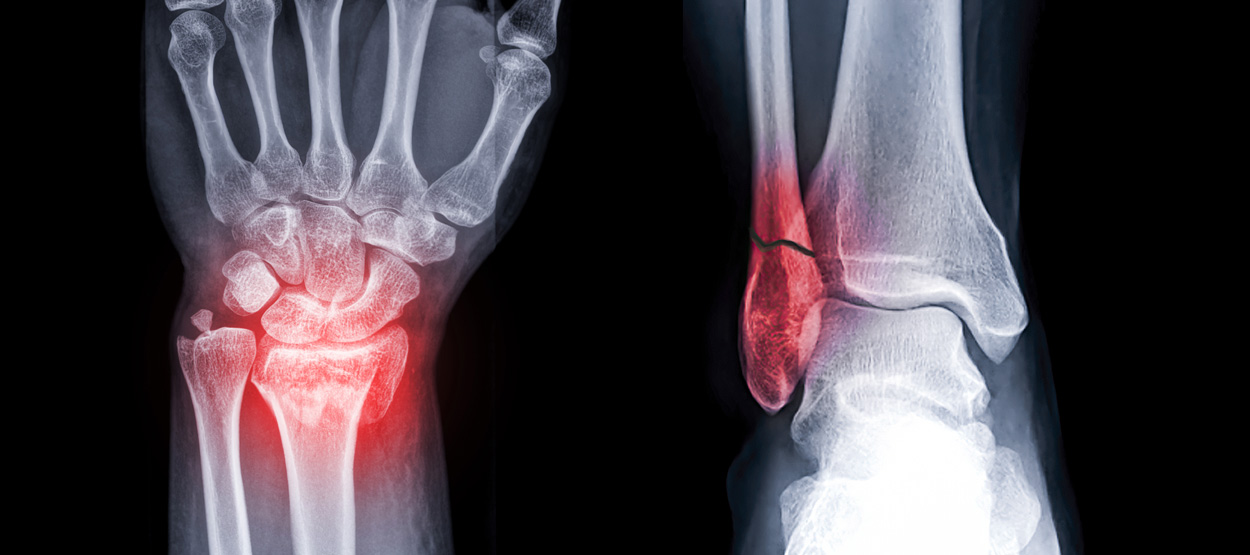

뼈에 금이 가거나 부러진 상태를 말합니다. 외부 충격, 낙상, 교통사고 등 다양한 원인으로 발생할 수 있으며,

모든 연령대에서 발생 가능하지만 특히 어린이와 노인에게서 흔하게 발생합니다.

손목 골절